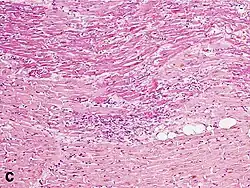

Micrograph of a myocardial infarction (ca. 400x H&E stain ) with prominent contraction band necrosis.

Histopathological examination of the heart may reveal infarction at autopsy. Gross examination may reveal signs of myocardial infarction.

Under the microscope, myocardial infarction presents as a circumscribed area of ischemic, coagulative necrosis (cell death). On gross examination, the infarct is not identifiable within the first 12 hours.[22]

Although earlier changes can be discerned using electron microscopy, one of the earliest changes under a normal microscope are so-called wavy fibers.[23] Subsequently, the myocyte cytoplasm becomes more eosinophilic (pink) and the cells lose their transversal striations, with typical changes and eventually loss of the cell nucleus.[24] The interstitium at the margin of the infarcted area is initially infiltrated with neutrophils, then with lymphocytes and macrophages, who phagocytose ("eat") the myocyte debris. The necrotic area is surrounded and progressively invaded by granulation tissue, which will replace the infarct with a fibrous (collagenous) scar (which are typical steps in wound healing). The interstitial space (the space between cells outside of blood vessels) may be infiltrated with red blood cells.[22]

These features can be recognized in cases where the perfusion was not restored; reperfused infarcts can have other hallmarks, such as contraction band necrosis.[25]